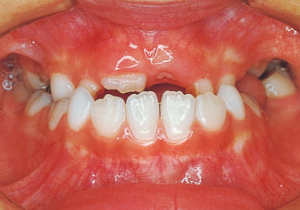

Age at Initial Visit: 8 years 1 month, Female / Protruding lower bite. Protruding lower jaw

1 Initial Visit 8-29-’79

Although there were many missing deciduous teeth, the number of permanent teeth was not problematic (4). The amount of negative overjet was significant (1). On cephalometric radiographs, the mandibular ramus was not relatively long, but the large gonial angle and the long mandibular body were noticeable, indicating an overall tendency of the mandible to project inferiorly and anteriorly. High lower facial height was also characteristic.

A potential predisposition to mandibular protrusion was clearly evident.